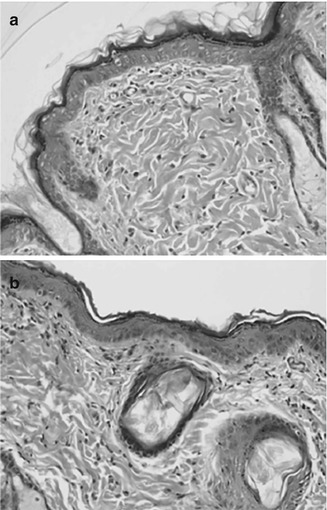

Fig. 8.4

Hematoxylin and eosin stained slides of (a) control skin and (b) electroporated skin 4 days after pulsing with 10× (1000 V for 100 μs). No occurrence of inflammation or tissue necroses was detected following electroporation treatment (Reproduced from Dujardin et al. 2002, 226. With kind permission from Elsevier Inc., USA)